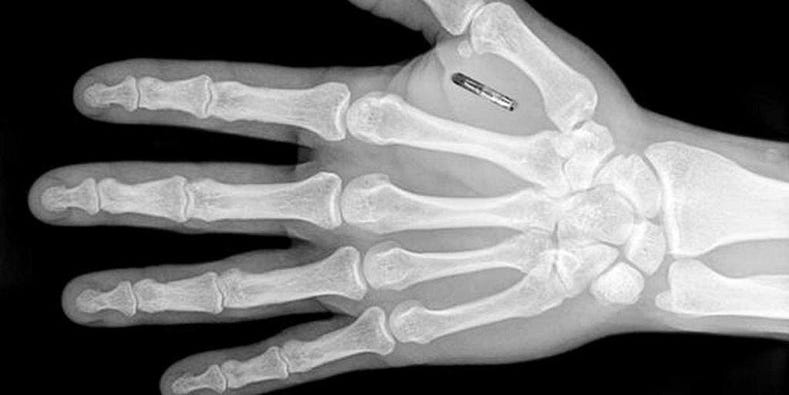

In ogni caso, eccolo qui, proprio davanti alla nostra porta di casa. E questa volta le tecnologie disponibili promettono di rendere la sua applicazione facile e assoluta. Mentre osservavo lo sviluppo di queste cose nel corso degli anni, mi sono chiesto che forma potesse assumere il "marchio della bestia". Cinquant'anni fa pensavo che potesse essere un tatuaggio a inchiostro, poi con lo sviluppo di tecnologie più recenti ho pensato che potessero essere i codici a barre che hanno iniziato a comparire su tutto alla fine degli anni '70, poi i codici QR, e infine i minuscoli chip RFID che potevano essere impiantati sotto la pelle. Già in uso per identificare animali domestici e da allevamento e determinare la loro proprietà, sembra il dispositivo ideale per l'identificazione positiva e la tracciabilità anche degli esseri umani. Che bella sostituzione per i badge identificativi, o le patenti di guida, o le carte di credito che potrebbero essere perse o rubate o falsificate. Non ci sarà bisogno di chiedere ai vostri ex medici le vostre cartelle cliniche, sarà tutto lì sul vostro chip insieme ad ogni altro dettaglio della vostra storia personale a cui le autorità potrebbero richiedere l'accesso. Che convenienza! Che sicurezza!

Sapevate che dal 6 aprile 2016 tutti i cani in Inghilterra, Scozia e Galles devono essere muniti di microchip? L'uso dei chip in HUMANS è già iniziato. In effetti, ci sono stati numerosi casi di persone che hanno scelto volontariamente di usare il chip solo per la comodità di poter entrare nei locali notturni o nei luoghi dei concerti, e molti datori di lavoro aziendali stanno valutando attentamente le possibilità di controllare l'accesso dei dipendenti alle informazioni sensibili e alle strutture sicure.

Non che i pericoli di abuso siano stati completamente trascurati. Un articolo del 4 febbraio 2020 di Market Watch riportava che "...Sono passati tre anni da quando i lavoratori di un'azienda del Wisconsin hanno volontariamente inserito microchip nelle loro mani, ed è probabile che ci siano "più aziende là fuori, ma probabilmente non lo stanno pubblicizzando...". Può sembrare incoraggiante che, come riporta lo stesso articolo, undici Stati abbiano approvato leggi "che vietano alle aziende di costringere i lavoratori a impiantare microchip nel loro corpo". Ma non dovremmo trarre grande conforto da ciò, sapendo che ci sono altri incentivi più sottili che possono essere applicati per ottenere la conformità, soprattutto quando i posti di lavoro diventano più scarsi nell'economia post-pandemica.